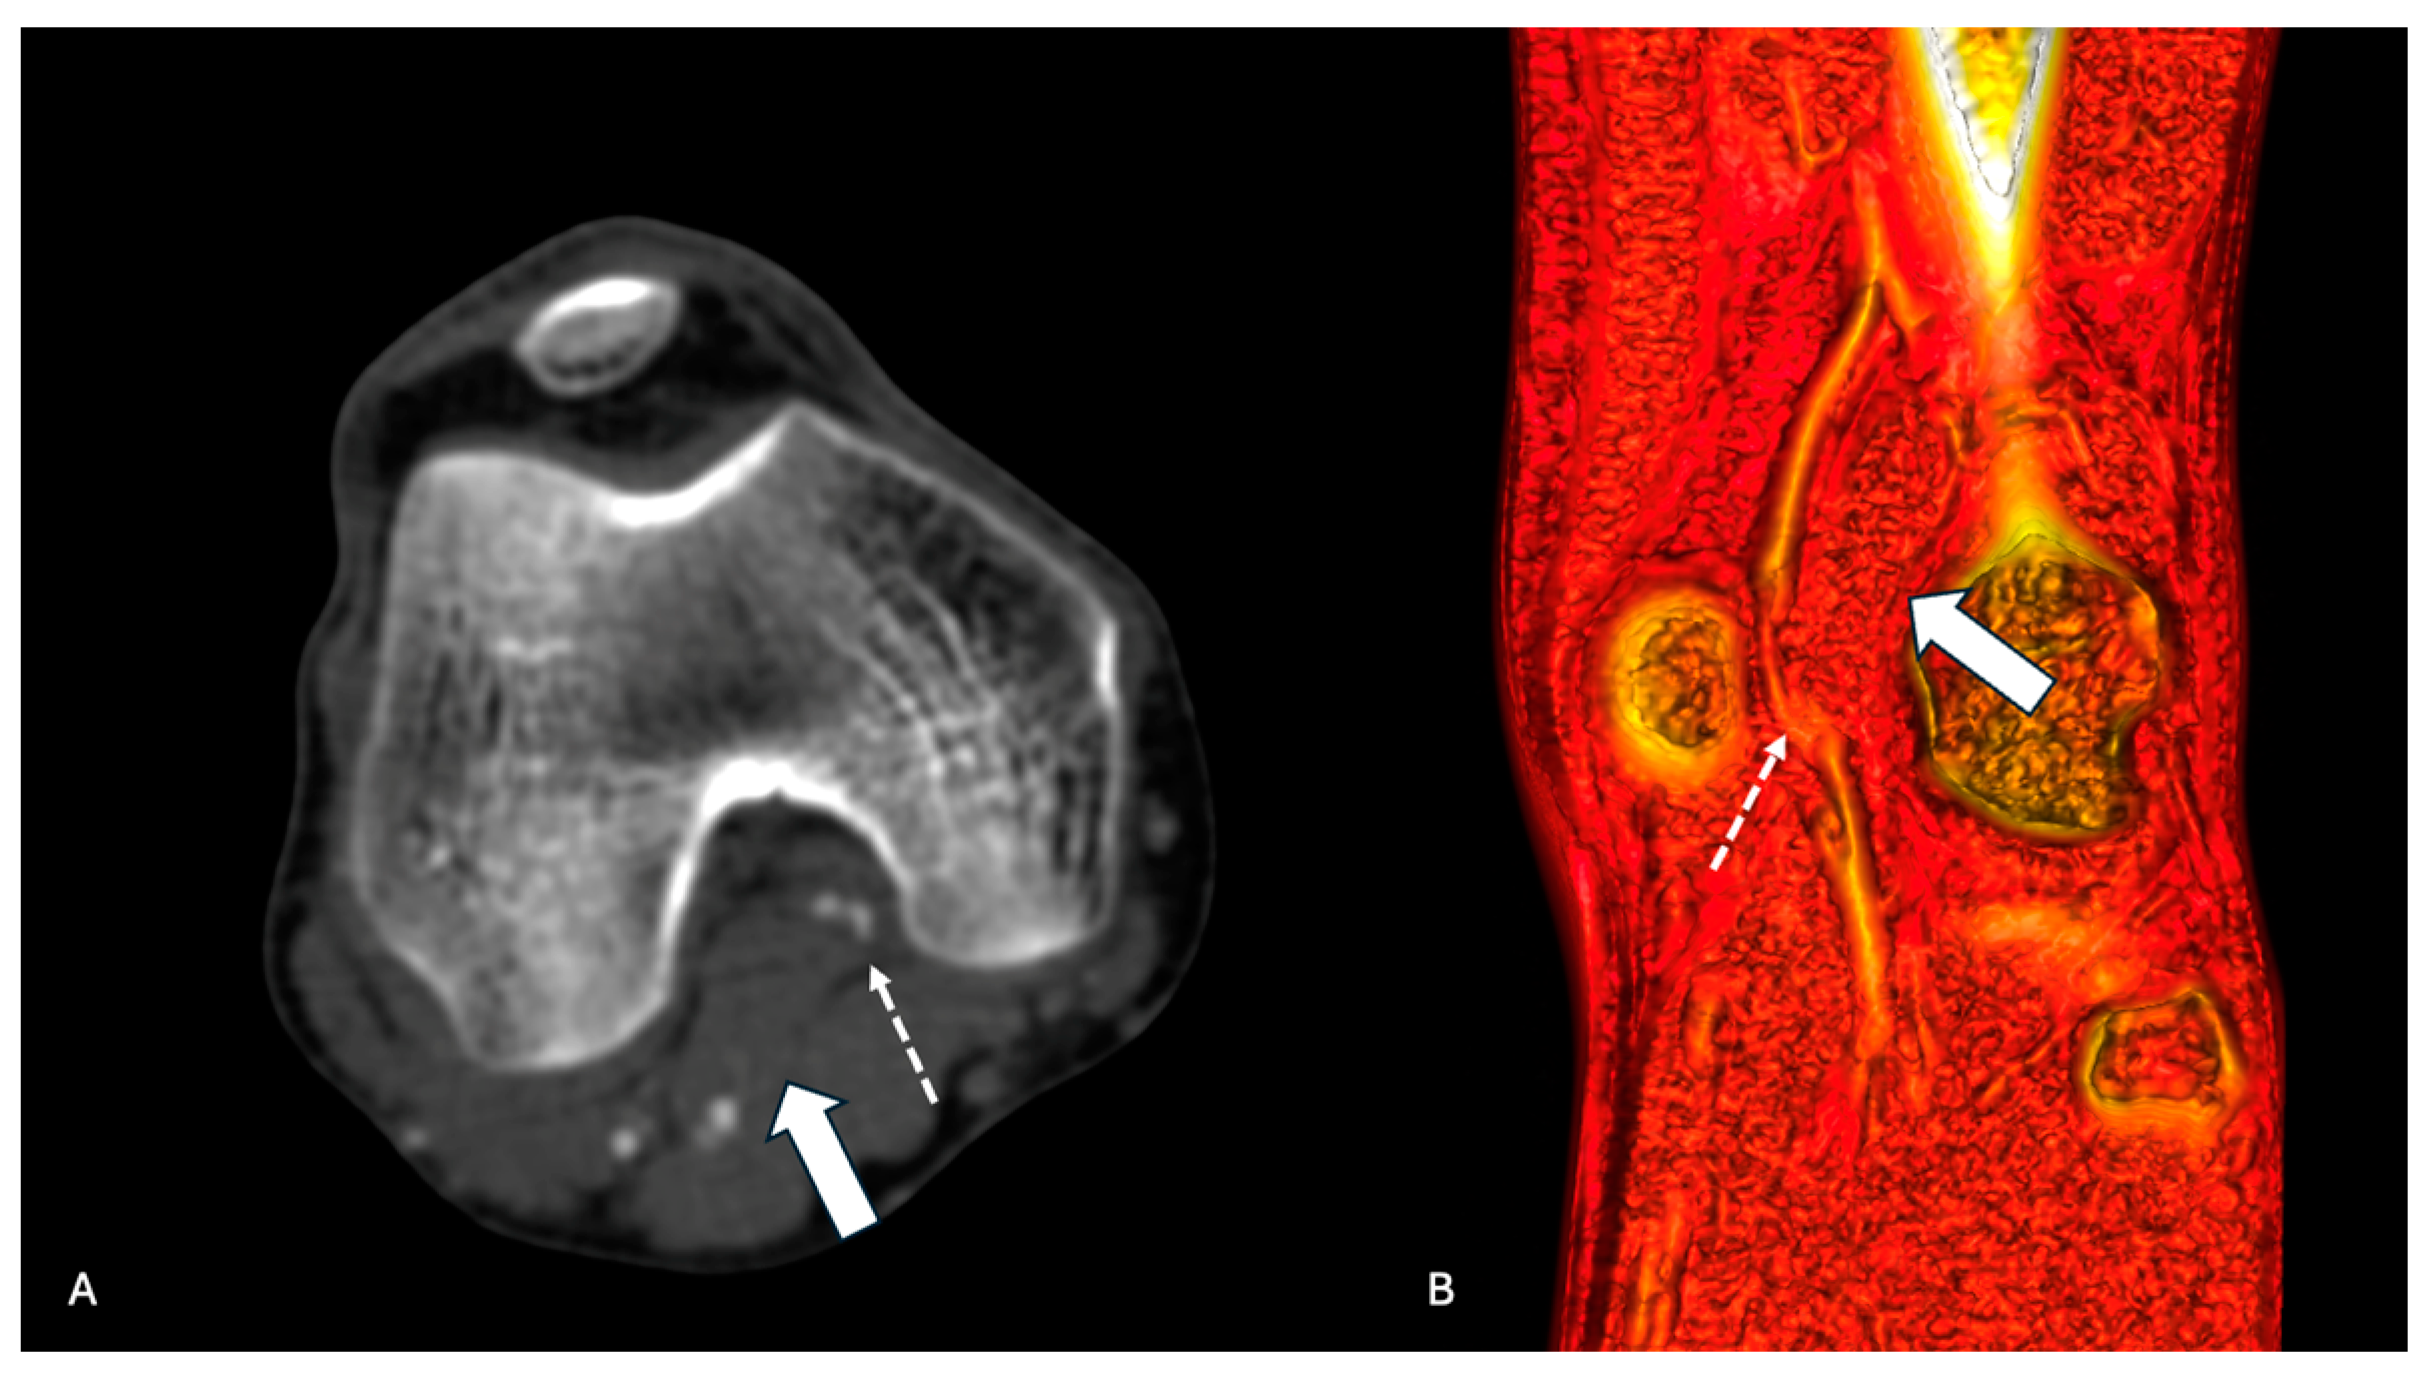

The sensitivity to the detection of PAES was 96.2% for DSA with dynamic maneuvers, 54.5% (12 limbs) for MRA, and 51.7% (29 limbs) for CTA (Figure 1 and Figure 2).

Figure 2. CTA of left inferior limb in a patient with PAES. (A) Coronal section of CTA showing anomalous insertion of the medial head of gastrocnemius (arrow) and occluded popliteal artery (dotted arrow). (B) Sagittal volume rendering showing anomalous insertion of the medial head of gastrocnemius (arrow) and occluded popliteal artery (dotted arrow).